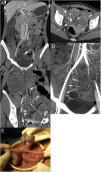

The presence of an MD in a MDCT should be suspected when a blind tubular structure connected to the terminal ileum by a neck of variable size is observed. Multiplanar 2D reconstructions images and CT enterography can help in the diagnosis. In patients with symptoms of obstruction or intestinal inflammation, the possibility of a complication secondary to a MD should be considered, especially when the terminal ileum and the vermiform appendix are normal. MDCT angiography, in cases of acute gastrointestinal bleeding, can identify contrast extravasation and accumulation of blood in the MD, and could demonstrate the persistent omphalomesenteric artery, which is diagnostic of MD. Other MDCT findings such as the presence of enteroliths or associated inflammatory changes around the MD can facilitate the preoperative diagnosis of MD complications.